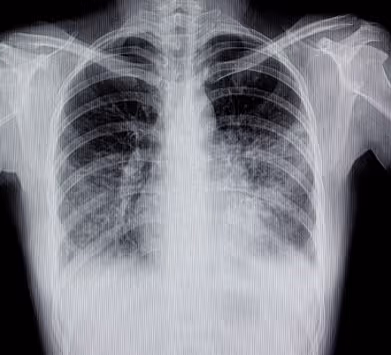

Nem sempre o agente etiológico é possível de identificar com exames, então se liga nessa dica: existem alguns tipos de pneumonia, em que podemos relacionar a anatomia com o agente:

- Lobar ou típica (mais cai em provas e na prática). Principal agente aqui é o Streptococcus pneumoniae (exceto em RN).

Diagnóstico de Pneumonia

Sobre o diagnóstico de pneumonia o Ministério da Saúde tem adotado que seja feito por síndromes clínicas (sinais e sintomas clínicos), tendo como principais sinais para suspeitar: tosse e/ou dispneia.